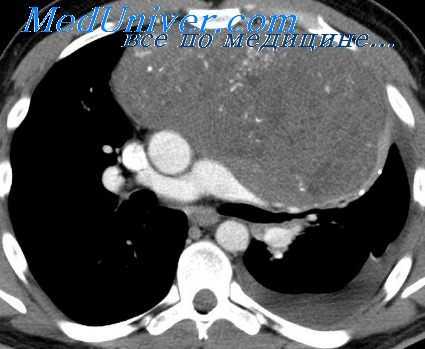

Прежде всего мы отбросили диагноз «тимома», с чем больной был направлен в институт. Против злокачественной тимомы свидетельствовало общее хорошее состояние больного без каких-либо признаков компрессии органов средостения (особенно крупных сосудов) при наличии огромной опухоли, занимающей почти все пространство от передней стенки грудной клетки до трахеи. Кроме того, на томограммах в прямой и боковой проекциях выявляется как бы конгломерат узлов, расположенных на различной глубине средостения, на что указывает и симптом «кулис».

Рентгенологическая картина с выраженным двусторонним поражением множества лимфатических узлов средостения на различной глубине давала больше оснований для диагноза лимфосаркомы.

При проведении курса рентгенотерапии оказалось, что данная опухоль довольно чувствительна к ионизирующему излучению, так как через 20 дней (после суммарной дозы в 4000 г) было отмечено значительное ее уменьшение, а через 40 дней (6000 г) она полностью исчезла.

Из литературы известно, что лимфосаркомы еще более рентгеночувствительны. Поэтому результаты рентгенотерапии при учете всех других симптомов позволяли нам остановиться на диагнозе лимфогрануломатоза, чувствительность которого примерно соответствует чувствительности опухоли в данном случае.